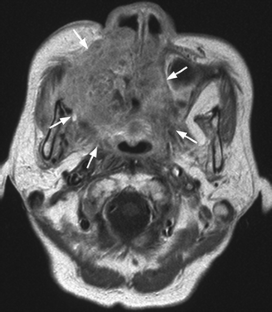

Fig. 5